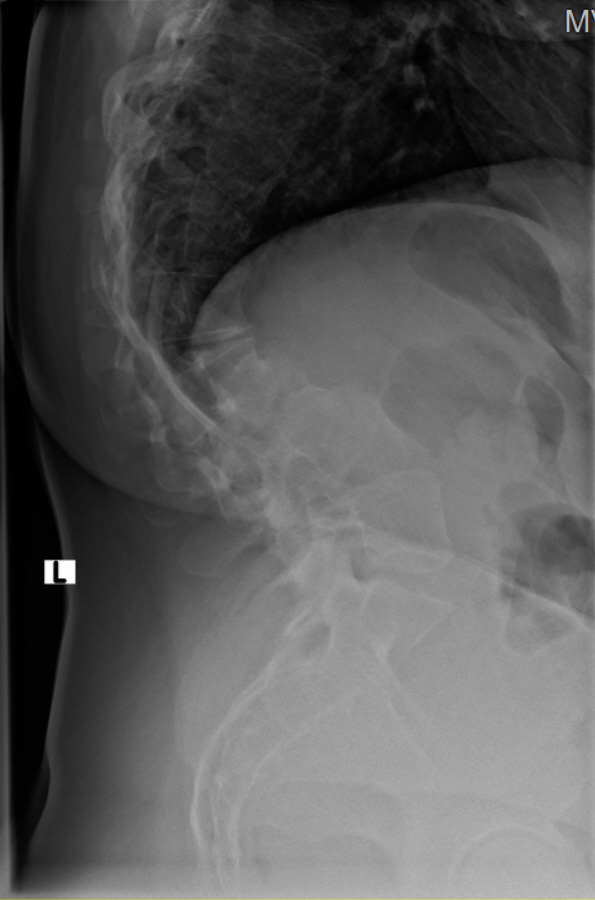

Thorakolumbalskoliose mit aktuellen COBB-Winkeln von 80 und 60 Grad...wenig Schmerzen und daher meistens glücklich

Viele kennen sich aus, daher möchte ich euch meine aktuellen Röntgenbilder nicht vorenthalten und hänge sie unten an.

Ich war beim MVZ Gersthofen, dort wurden die Röntgenbilder gemacht…die massive Verschlechterung war sehr offensichtlich

Dort wurden die Winkel gemessen, unten 80 Grad und oben 60 Grad…eine Verschlechterung von über 2 Grad pro Jahr, wenn man es auf die ganze Zeit berechnet

Die Winkel hab ich nachgemessen, wie der Arzt der Hessing und hier mal als Screenshot